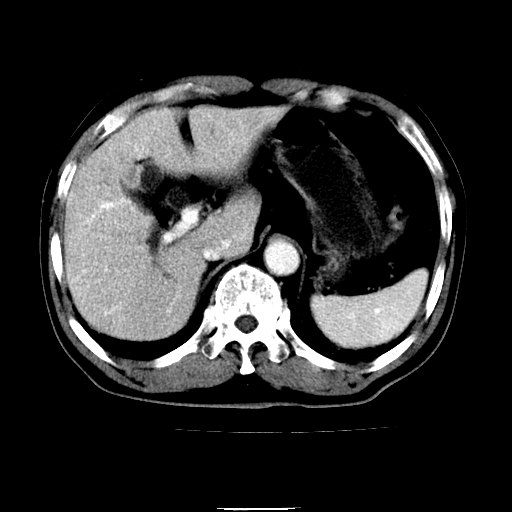

以下是引用chenqiong在2010-3-25 20:56:00的发言:[br]1、胆囊炎,胆囊息肉[br]2、肝内胆管及胆总管扩张,胆总管下端结石[br]3、十二指肠乳头旁憩室

以下是引用zxl51642在2010-3-26 10:47:00的发言:[br]胆囊炎,胆囊息肉,胆总管扩张,但未看到明显肿块,肝内胆管扩张不像恶性,炎性狭窄或阴性结石可能吧,建议mrcp,右肾小囊肿